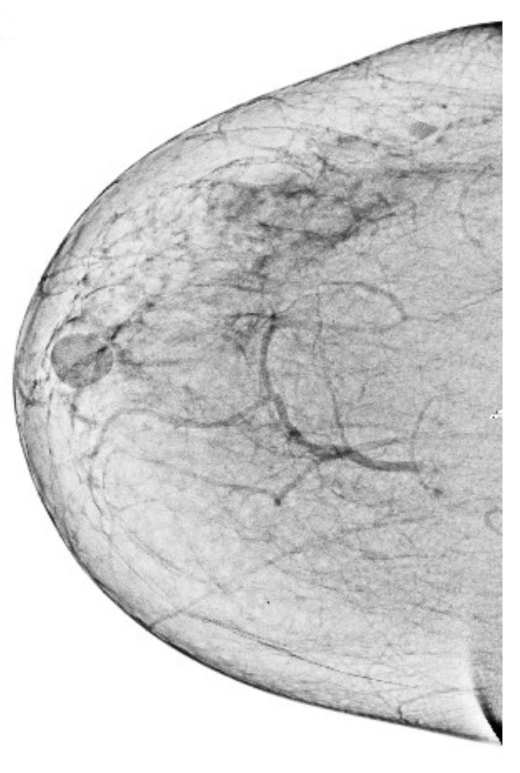

We also measured the PSNR, the image contrast, and the EME of each category of databases, as we analyzed the image in terms of visual observation. The Table 3 shows the performance of our proposed image enhancement method. It can be seen from the Table 3 that our proposed method improved PSNR, contrast, and EME, and this also shows that our method can work on every category of BI-RADS. Because many techniques do not work on higher grade BI-RADS due to the complexity and the images are not of good quality. We obtained an average improvement in PSNR, contrast, and EME in the Table 4. For more observations, we analyzed the visual image of each category and we analyzed the CC and MLO of each category as shown in the Figure 7, Figure 8, Figure 9, Figure 10, Figure 11, Figure 12, Figure 13, Figure 14, Figure 15 and Figure 16. From the figures, every detail of image of every category can be observed, leading to better segmentation of the abnormal region. This image enhancement technique can be used as preprocessing steps for the detection of breast cancer. It is a very fast processing algorithm and it takes on 21.13 s. It gives opportunity to medical experts to analyze the mammogram images very quickly to propose the timely treatment.

Figure 15.

Analysis of CC view of BI-RADS-5 mammogram images.

Figure 16.

Analysis of MLO view of BI-RADS-5 mammogram images.